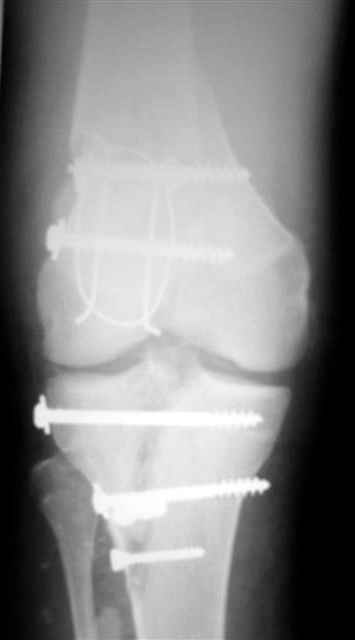

Re: открытый перелом мыщелков бедра, латерального

Вид раны на сегодня...

4 cутки после травмы.